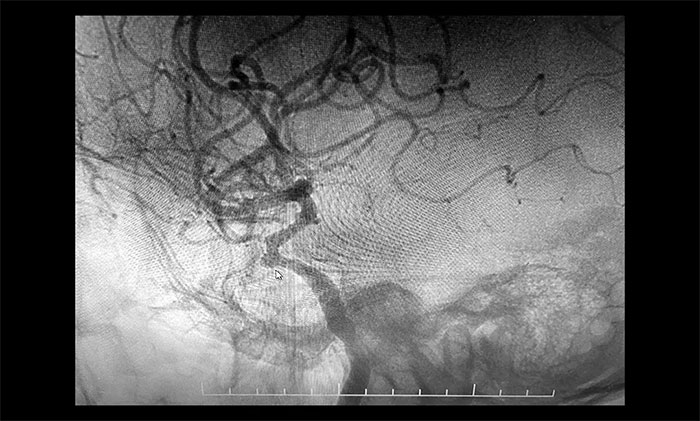

于耀宇主任为患者完善检查,CTA提示右侧颈内动脉C4段可疑小丘样隆起,不排除动脉瘤。为进一步明确诊断,于耀宇主任在导管室局麻下为患者行DSA脑血管造影以明确诊断,结果显示:右侧颈内动脉C4段可见3mmx3.5mm宽颈动脉瘤,海绵窦段可见轻度狭窄。

▲ 右侧颈内动脉C4段见动脉瘤